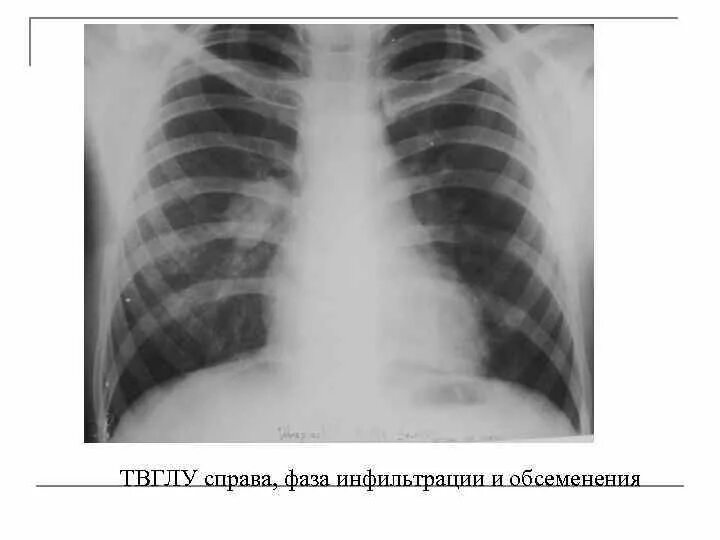

Бронхоаденит это